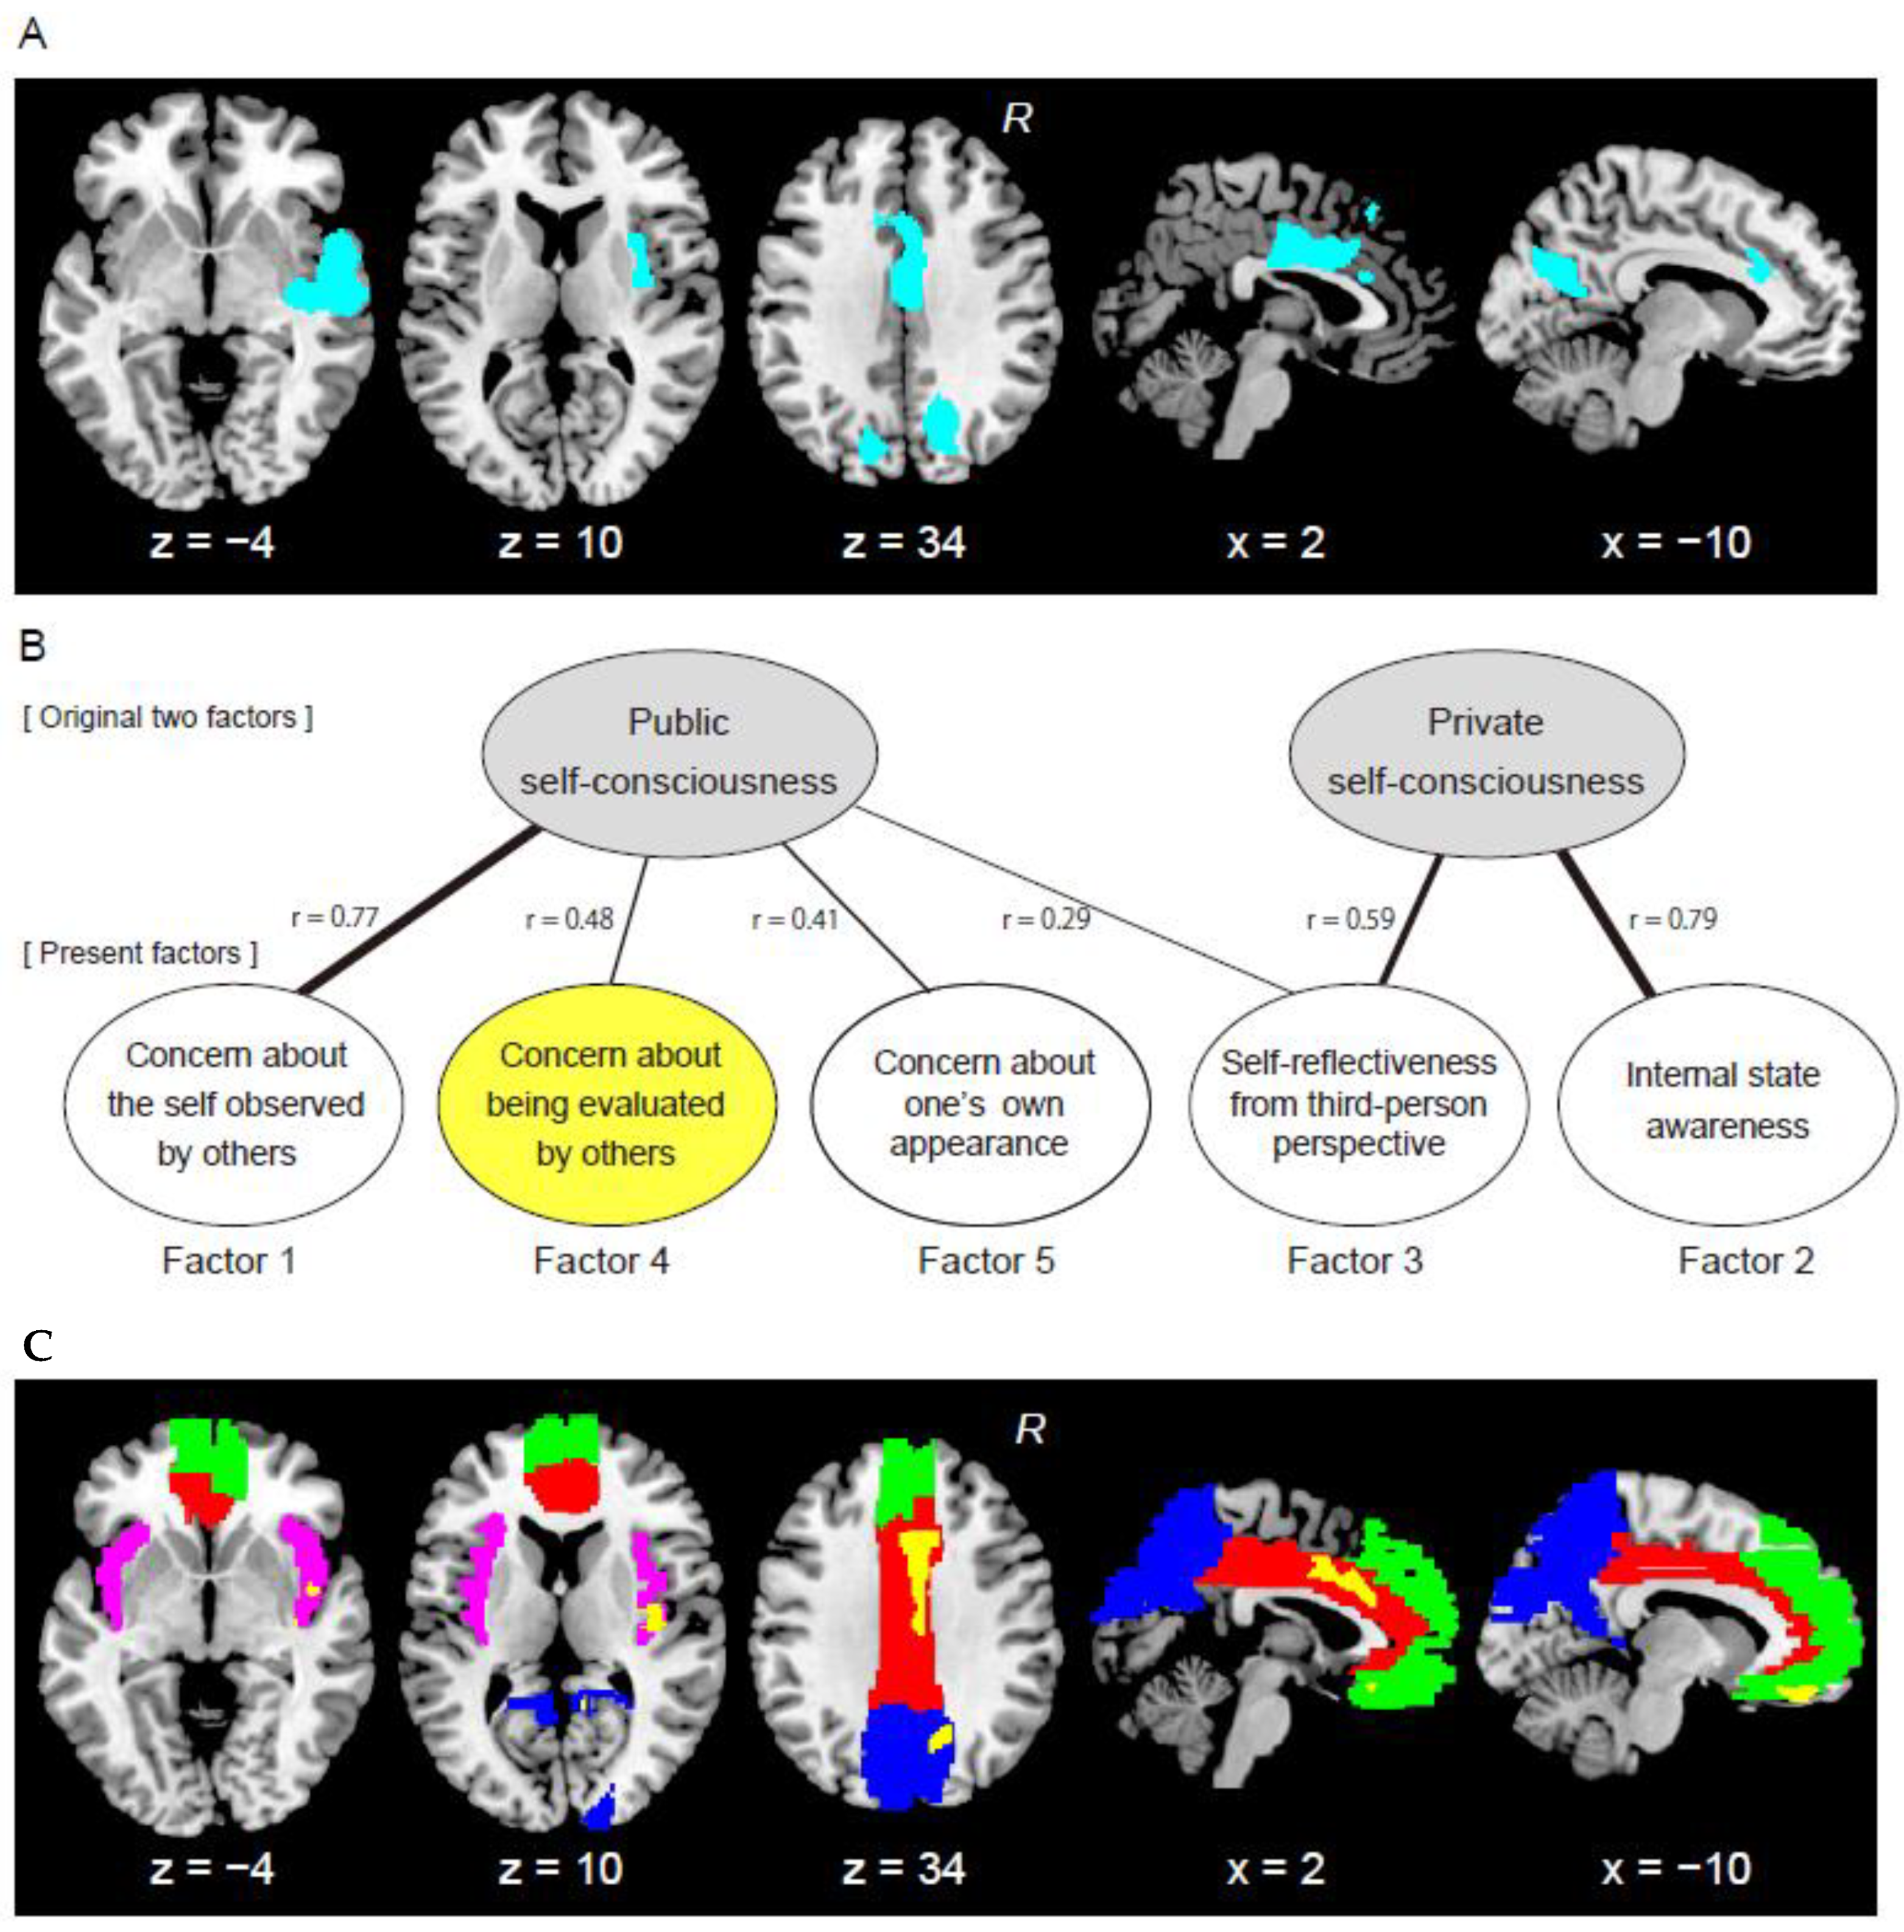

3.1. Results from Whole-Brain Analysis

3.2. Results from Factor Analysis

3.3. Results from ROI Analysis

| Clusters | Number of Voxels | Cluster-Level p (Corrected) | MNI Coordinates | T-Value | Anatomical Identification (Cytoarchitectonic Map) | ||

|---|---|---|---|---|---|---|---|

| x | y | z | |||||

| Cingulate cluster | 2172 | 0.03 | 3 | −2 | 33 | 3.94 | Rt MCC |

| −12 | 24 | 32 | 3.27 | Lt MCC | |||

| 0 | 27 | 50 | 3.09 | Superior medial gyrus | |||

| −6 | 27 | 24 | 3.02 | Lt ACC | |||

| 2 | 26 | 23 | 2.98 | Rt ACC | |||

| Rt temporal cluster | 4206 | <0.001 | 56 | −6 | −3 | 4.77 | Superior temporal gyrus (Area TE 1.2) |

| 50 | −17 | 0 | 4.34 | Superior temporal gyrus | |||

| 56 | 8 | −8 | 4.13 | Temporal pole (Area TE 3) | |||

| 42 | −20 | −6 | 3.90 | Insula (Area Id1) | |||

| 57 | −20 | −11 | 3.67 | Middle temporal gyrus | |||

| 33 | −3 | 14 | 3.47 | Insula | |||

| 35 | −14 | −3 | 3.45 | Insula (Area Ig2) | |||

| 53 | 8 | −30 | 2.92 | Temporal pole | |||

| Rt precuneus cluster | 2359 | 0.02 | 17 | −75 | 27 | 4.27 | Cuneus |

| 11 | −53 | 23 | 4.19 | Precuneus | |||

| 24 | −69 | 23 | 4.02 | Superior occipital gyrus | |||

| Lt precuneus cluster | 1859 | 0.06 | −15 | −57 | 26 | 4.40 | Cuneus |

| −17 | −68 | 30 | 4.07 | Superior occipital gyrus | |||

| −14 | −53 | 18 | 3.60 | Precuneus | |||

| ROIs | Number of Voxels | Cluster-Level p-Value (Corrected) | MNI Coordinates | T-Value | ||

|---|---|---|---|---|---|---|

| x | y | z | ||||

| Brain regions with gray-matter expansions in individuals with high scores on Factor4 | ||||||

| ACC/MCC | 1342 | 0.01 | 11 | 20 | 26 | 3.74 |

| Insula | 534 | 0.07 | 41 | −14 | 3 | 3.55 |

| Precuneus/cuneus | 1080 | 0.03 | 12 | −48 | 20 | 4.12 |

| MPFC | 633 | 0.08 | −5 | 42 | −21 | 3.82 |